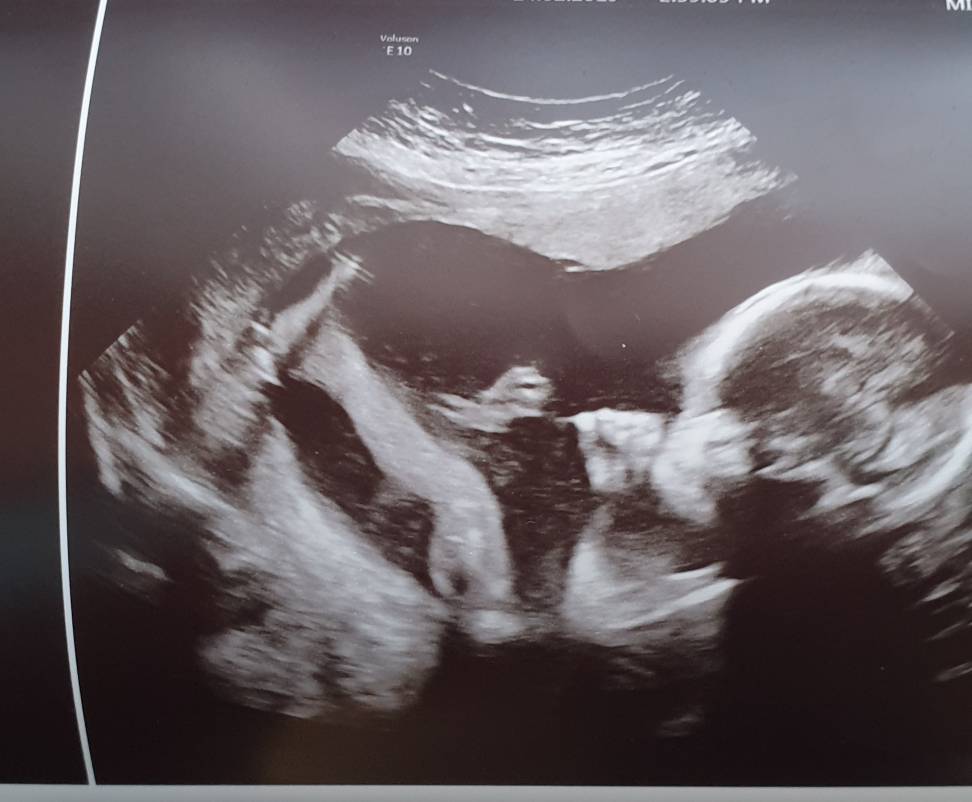

Moj Ksieciunio ma sie dobrze, ale nerki troszke za male. Sa w dolnej granicy limitu i mamy narazie sie nie martwic. Za 8 tyg.kolejne usg. A dzisiaj mialam specjaliste i jakiegos doktora seniora. Usg trwalo i trwalo, nawet jajniki mi sprawdzali.

Ciesze sie ze zgodzilam sie na te badania, tak dokladnie z Julka mnie nie badali.

Mlody machal, ziewal i ssal kciuka. A nogi ma dlugie jak przystalo na maratonczyka. W koncu przesiedzial w brzuchu jak bieglam polowke [emoji6]Zobacz załącznik 942884Zobacz załącznik 942885